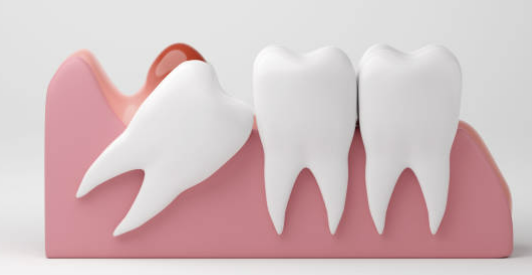

안녕하세요. 사랑니를 발치한 후에는 상처가 잘 아물도록 적절한 식습관을 유지하는 것이 매우 중요합니다. 무리한 식사는 출혈, 감염, 통증 등을 유발할 수 있으므로 주의해야 합니다. 지금부터 사랑니 발치 후 안전하게 식사하는 방법과 피해야 할 음식에 대해 자세히 알아보겠습니다.

사랑니 발치 후에는 상처 부위가 매우 민감하며 잘못된 식습관이 회복 속도를 늦출 수 있습니다. 올바른 식사 습관을 유지하면 통증을 줄이고 감염 위험을 낮추며 빠른 회복을 돕습니다.